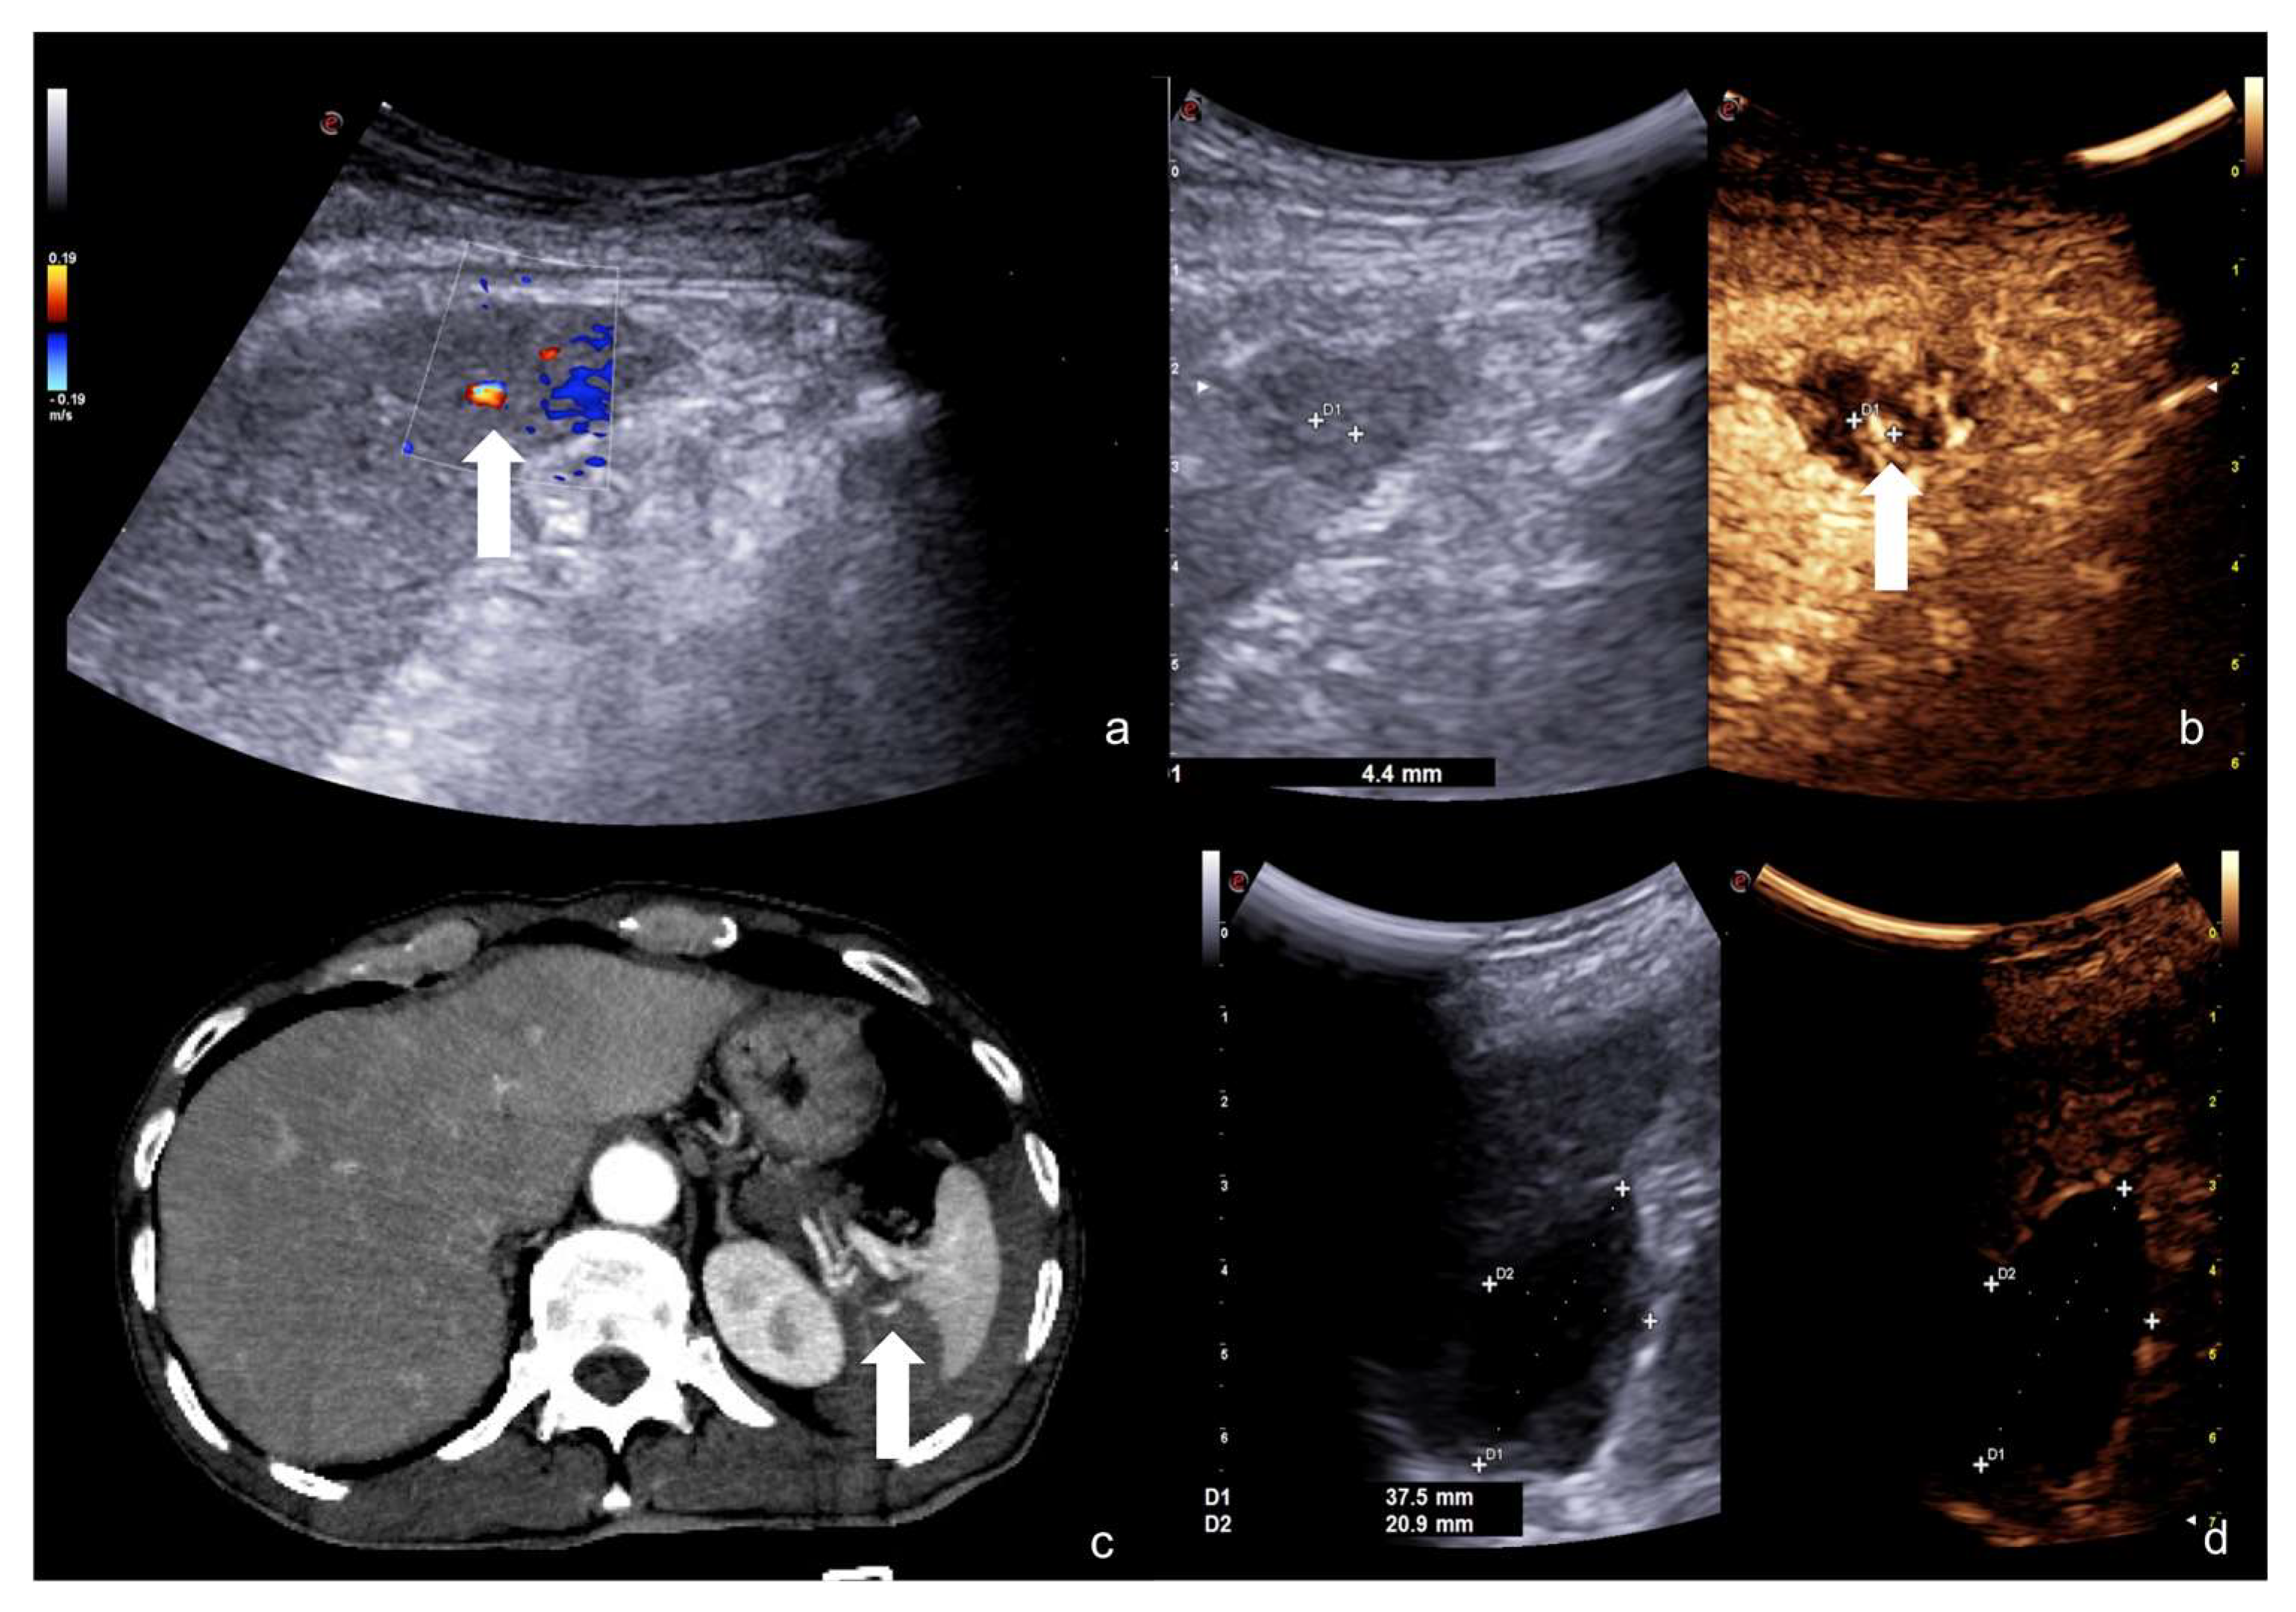

“Turn on the light”: CEUS is more sensitive than US for the detection of solid organ injuries (Figure 23).

Figure 23.

Sub-Glissonian hepatic hematoma in a 40−year-old woman. At B-mode US study (a,b, split image on the left), no definite hematomas was showed. At CEUS evaluation (a,b, split image on the right), the presence of a small sub-Glissonian hematoma was clearly delineated (arrow). Contrast-enhanced CT examination (c, axial and d, coronal view) confirmed the presence of the small non-bleeding sub-Glissonian hematoma (arrow).

4.3. Step 3

Figure 24.

An example of multimodal visualization of post-traumatic splenic PSA (white arrows) at CD–US (a), CEUS (b), and arterial phase contrast-enhanced CT scan (c); CEUS follow-up examination after embolization (d) showed no evidence of residual PSA.

Figure 25.

Splenic trauma in car accident with small splenic laceration visible on contrast-enhanced CT scan performed at emergency department (a,b, white arrowhead). CEUS examination performed 4 days after trauma confirmed the splenic laceration (c, white arrowhead); subsequent Flash mode CEUS (d) revealed multiple, small and diffuse intra-splenic PSAs (white arrows) not shown at admission arterial phase CT exam (a); these findings were confirmed at contrast enhanced CT scan (e, arrows) and angiography (f, arrows).